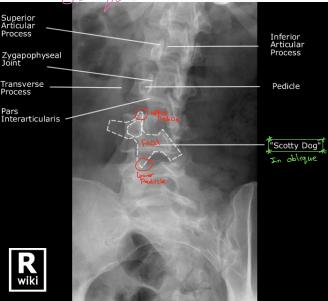

Anatomical Structures Visible on Oblique View

- Superior Articular Process

- Zygapophyseal Joint

- Transverse Process

- Pars Interarticularis

- Inferior Articular Process

- Pedicle

“Scotty Dog” sign is visible on oblique radiographs